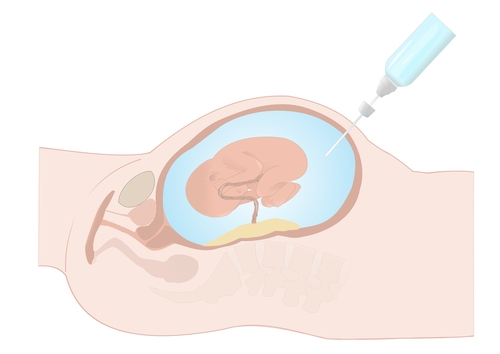

Amniocentesis is a diagnostic test to detect chromosomal abnormalities in the fetus.

When is it performed? Amniocentesis is performed after 15 weeks and takes a sample of fluid from around the baby. Amniocentesis is performed by passing the needle through the mother’s abdominal wall. A sterile technique is used to reduce the risk of infection and pregnancy loss.

CVS is performed between 11-14 weeks and takes a sample of tissue (the chorionic villi) from behind the placenta. CVS is performed by passing the needle through the mother’s abdominal wall. A sterile technique is used to reduce the risk of infection and pregnancy loss.

Amniocentesis: Amniocentesis is a diagnostic test to detect chromosomal abnormalities in the fetus and is performed after 15 weeks and takes a sample of fluid from around the baby. Amniocentesis is performed by passing the needle through the mother’s abdominal wall. A sterile technique is used to reduce the risk of infection and pregnancy loss.